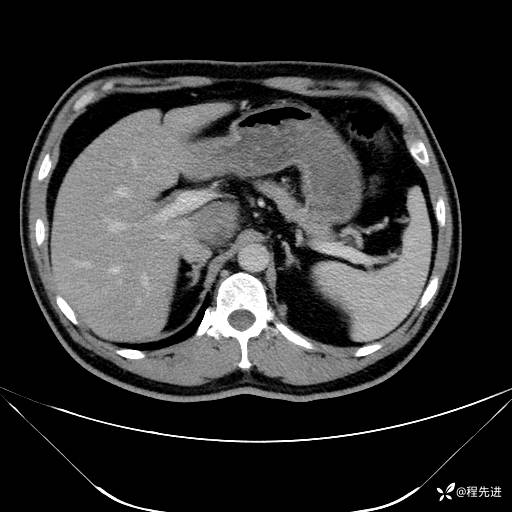

【腹盆】特别精彩病例|发现腹膜后肿物1月余

主诉:发现腹膜后肿物1月余

现病史:患者1月余前查体,行超声检查提示:后腹膜囊实性肿块;慢性胆囊炎伴胆囊内结石;无腹痛腹胀,不伴腹泻发热等;偶感腰背部酸痛。

CT平扫+增强: